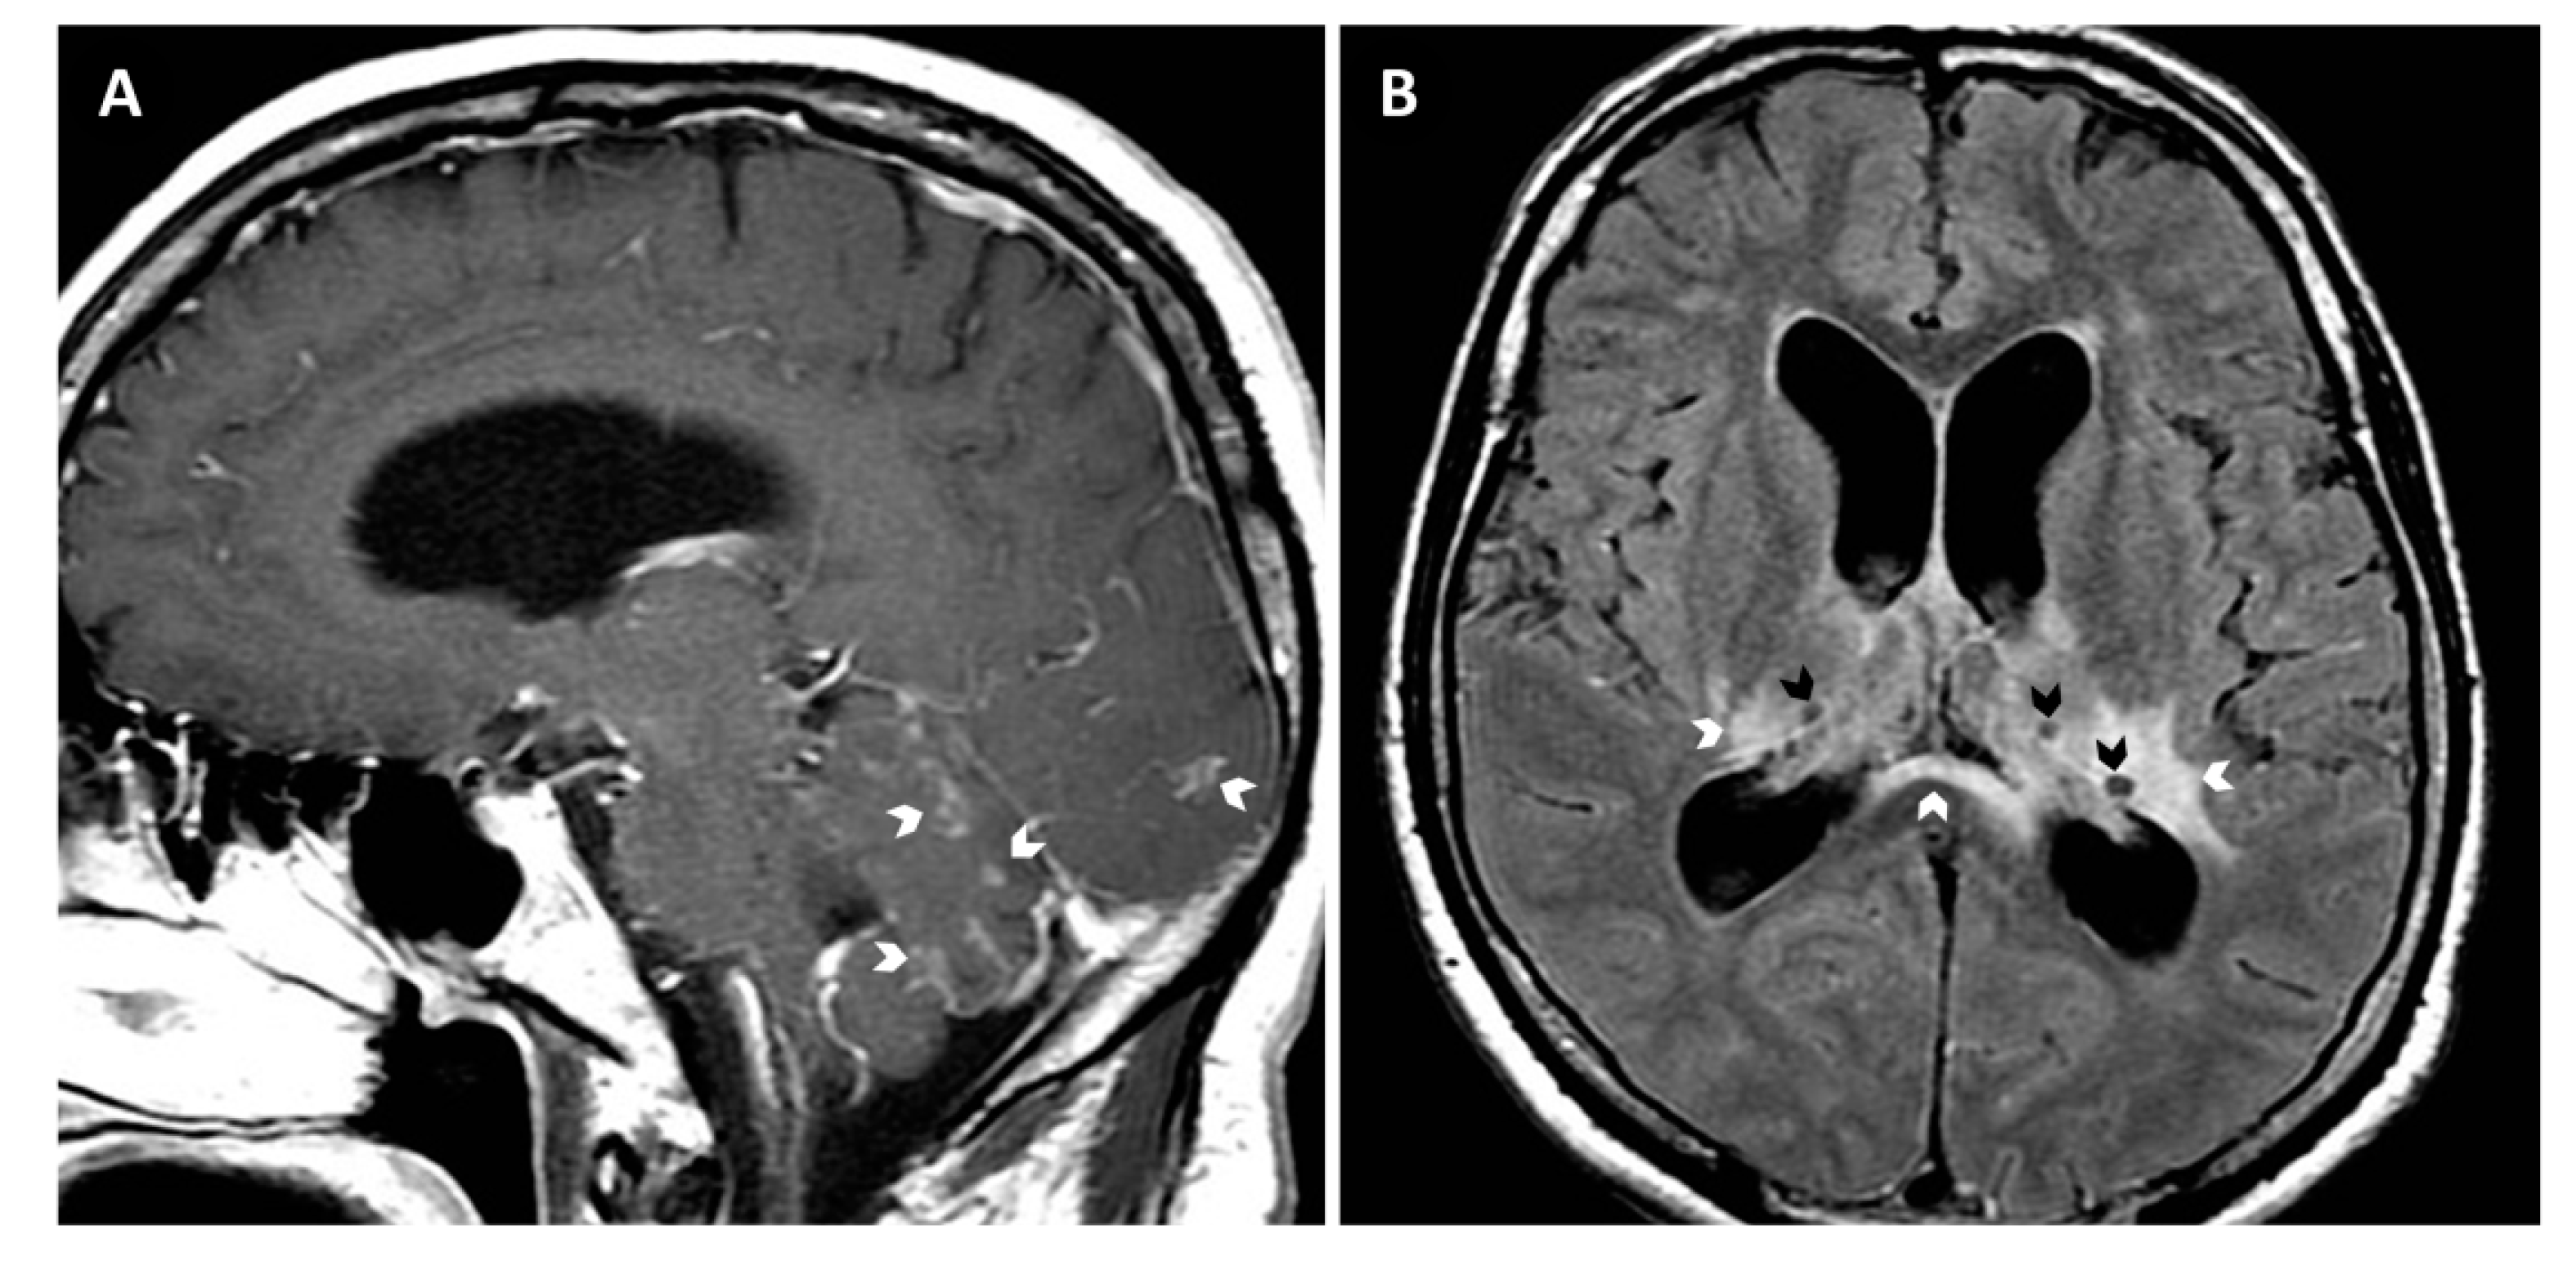

A 48-year-old previously healthy man from Santa Cruz, Bolivia, attended Clínica Alemana de Santiago (Chile) with a 12-months history of progressive neurological problems. Symptoms had started with malaise, tremor, and headache, later accompanied by dysphagia, dysphonia, singultus, progressive severe cognitive deterioration, and a weight loss of 10 kg. The patient denied former travel outside Bolivia; his visit to Chile was for medical reasons, i.e., evaluation of the current illness. At presentation, the patient was prostrated and showed severe memory disorder, right central facial paralysis, right brachial and crural paresis, and symmetric postural tremor. Routine laboratory exams were normal, including tests for HIV, syphilis, Histoplasma capsulatum, and tuberculosis. While a chest CT scan was unremarkable, brain MRI showed leptomeningeal infiltrates and hydrocephalus, together with ganglionar and periventricular edema and cystic lesions (Figure 1). Cerebrospinal fluid (CSF) examinations revealed low glucose (5 mg/dL), elevated protein (788 mg/dL), and pleocytosis (35 cells/µL, 97% mononuclear); cryptococcal antigen latex agglutination (CALAS®, Meridian Bioscience, Memphis, TN, USA) was positive (1:64); Ziehl Neelsen and India ink stains as well as Xpert MTB/RIF were negative. CSF cultures on Sabouraud agar showed small whitish colonies, which produced a blue color on canavanine–glycine–bromothymol blue agar, compatible with C. gattii species complex. MALDI-TOF mass spectrometry (VITEK MS, bioMérieux) confirmed the strain as “C. gattii” with the maximum confidence score (99.9%). PCR and subsequent restriction fragment length polymorphism (RLFP) analysis of the URA5 gene classified the strain as C. bacillisporus (VGIII). Further multilocus sequence typing (MLST) and specific PCR tests [10,11], performed at the Robert-Koch Institute in Berlin, Germany, grouped the strain as C. bacillisporus sequence type 79 (ST79). Antifungal susceptibility testing by microdilution using the Clinical and Laboratory Standards Institute (CLSI) M27 protocol [12] showed the following minimum inhibitory concentrations: amphotericin B (AMB), 0.125 µg/mL; flucytosine, 4 µg/mL; posaconazole, 0.5 µg/mL; voriconazole, 0.25 µg/mL; fluconazole, 32 µg/mL; and itraconazole, 0.25 µg/mL.

Figure 1. Brain MRI images (A, sagittal T1Gd and B, axial T2-FLAIR [fluid attenuated inversion recovery] showing generalized leptomeningeal enhancement (arrows in A), ganglionar and periventricular edema (white arrows in B), cystic lesions suggestive of gelatinous pseudocysts (black arrows in B), and enlarged ventricles compatible with communicating hydrocephalus.